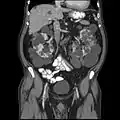

- Abdominal CT scan of an adult with autosomal dominant polycystic kidney disease: Extensive cyst formation is seen over both kidneys, with a few cysts in the liver, as well. (Coronal plane)